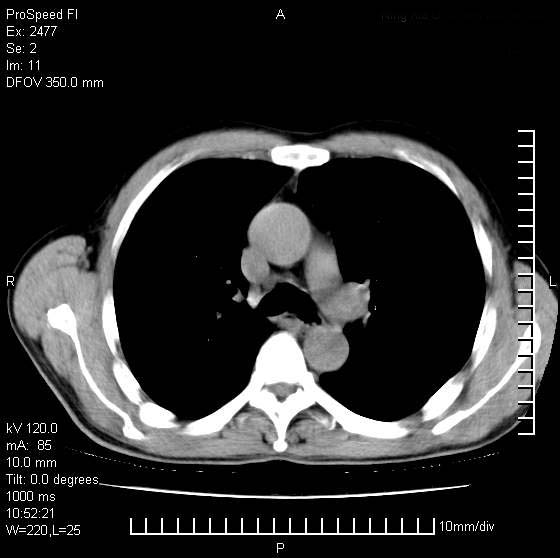

以下是引用天南地北在2007-10-9 14:29:00的发言:[br]1:右上肺结核[br]2:右肺下叶肿块:不支持肺癌,首先考虑炎性病变-肺脓疡可能性大[br]理由:1:临床病史支持,肺脓肿症状不明显应该是不规则服药造成。[br] 2:肿块边缘模糊,周围可见炎性渗出,长毛刺,内见支气管征,不过有点不规则。[br] 我感觉下肺癌这个诊断有点偏左,建议积极抗炎治疗后复查

以下是引用卜一在2007-10-9 15:55:00的发言:[br][br] [br] 1:右上肺结核[br]2:右肺下叶肿块:不支持肺癌,首先考虑炎性病变-肺脓疡可能性大[br]理由:1:临床病史支持,肺脓肿症状不明显应该是不规则服药造成。[br] 2:肿块边缘模糊,周围可见炎性渗出,长毛刺,内见空气支气管征,不过有点不规则。[br] 我感觉下肺癌这个诊断有点偏左,建议积极抗炎治疗后复查![br]支持! [br] [br] [br]

以下是引用wxy7406在2007-10-9 21:02:00的发言:[br]结合临床病史首先考虑感染性病变,但周围型肺癌不能除外,1.患者年龄偏大2.临床有咯血3.(也觉得是最重要的一点)病灶内有偏心性空洞。

以下是引用王仕学在2007-10-9 13:48:00的发言:[br]右下肺周围性肺癌可能性大,最好活检吧

以下是引用hhcckk在2007-10-9 15:18:00的发言:[br]右上肺病灶考虑结核,病灶多种形态并存(纤维化、增殖性病灶并存)[br]右下肺病灶比较难说,个人意见更趋向于“天南地北”的诊断----肺脓肿[br]1、病人有明显的寒战,高热,肿瘤病人很少出现[br]2、病灶周围的肺纹理走向柔和,没有肿瘤病灶常见的集束征[br]3、病灶边缘的毛刺较长,恶性肿瘤多为短毛刺[br]痰中血丝和病人的年龄是两个不利于良性肿块的因素,建议早点活检

以下是引用ydx_74在2007-10-9 15:53:00的发言:[br]右上肺结核,右下中心性肺癌可能大,肺门淋巴结肿大。